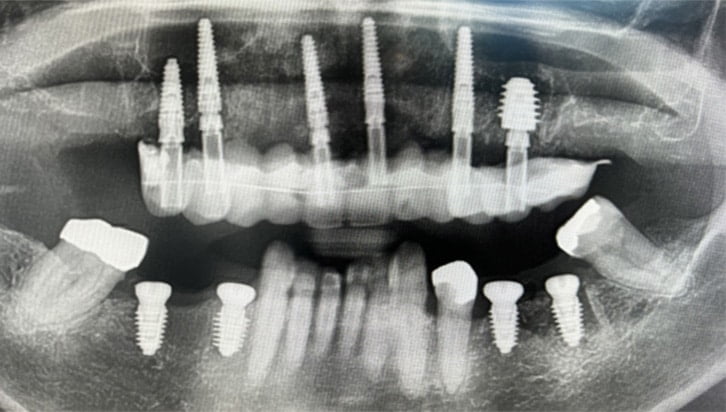

Dental Implant Cases

Aberdeen Implant Centre

Beautiful new smiles created at the Dental implant centre